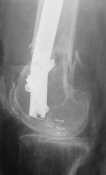

I presented a series of ~25 such cases at EuroTrauma'2004. Many cases were discussed here. I attach am example. Look also recent cases at http://www.hwbf.org/hwb/conf/alex58/scfx.htm,

http://www.hwbf.org/hwb/conf/alex63/alex63.htm

I do realize that you are master surgeon, and congratulations on another excellent, spectacular case (result), but,

- Your last posted case: how is possible to have secure fixation with applied construct without additional casting, bracing or Ilizarov?

THX, initial images are

1,

2.

At that moment we had in stock only the 10 mm solid nails so of course there was no idea about early weight bearing. But it was quite enough for early knee ROM excersises (see attached). Two locking screws through the distal block provided that.